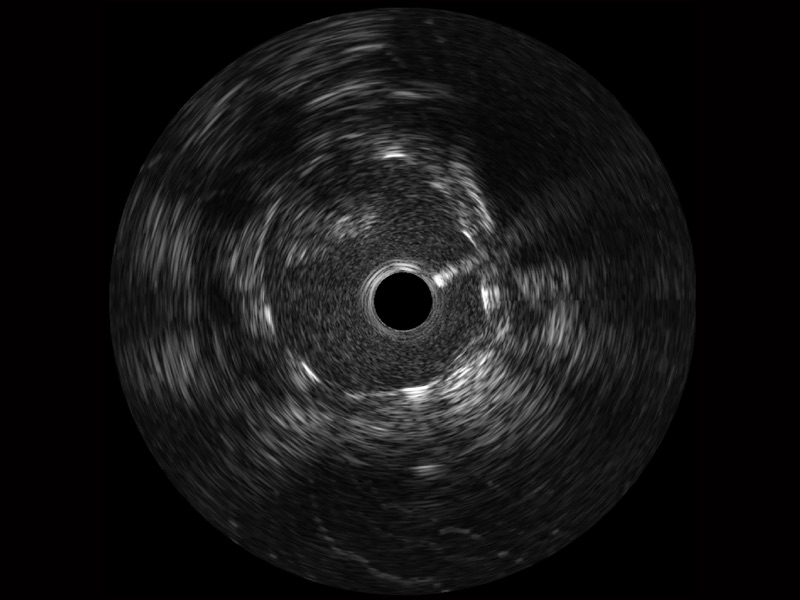

狗万官方网站宽频IVUS图像

传统IVUS图像

对比传统IVUS导管成像,狗万官方网站宽频IVUS图像的近场支架梁显影更细腻,远场中膜外血管仍清晰可辨,兼顾远中近,兼顾分辨力与穿透深度